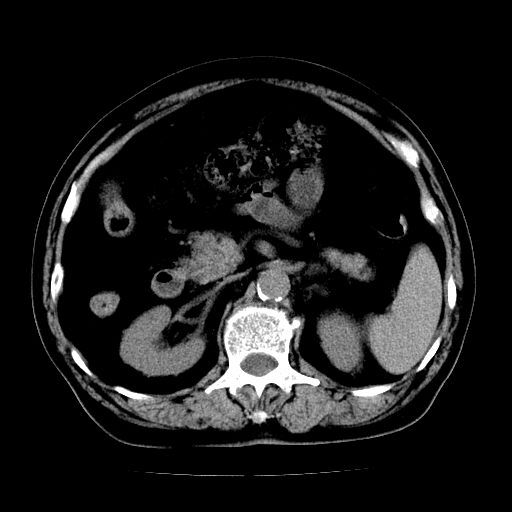

男,71岁,皮肤黄染四天。

肝内外胆管及胆总管上段扩张,考虑为梗阻所致,建议mrcp检查。

考虑胆总管癌并肝内外胆管扩张。

胰腺上端胆总管内见软组织影,强化不明显,结合临床,还是考虑低位梗阻性黄疸,胆总管癌可能性大